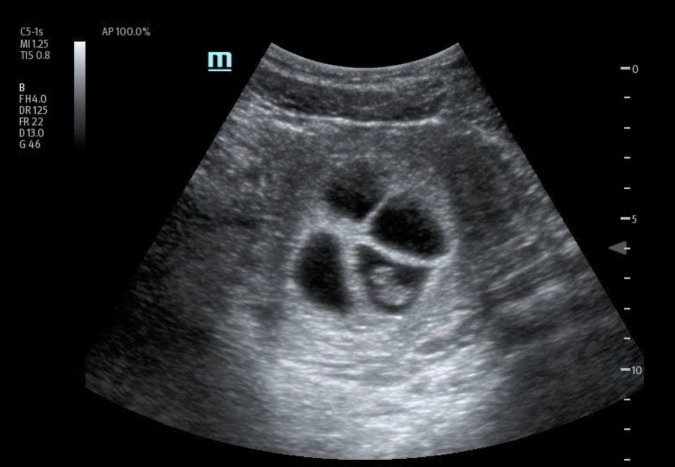

处理多胎妊娠具有挑战性,需要仔细评估。护理点超声检查(POCUS)已成为评估疑似头胎妊娠的潜在重要工具。然而,它在评估多胎妊娠中的作用仍不确定。我们介绍了一例 36 岁加纳女性的病例,她在接受体外受精后出现急性阴道出血。床旁经腹 POCUS 检查发现有四个宫内妊娠,胎儿有胎儿极和心脏活动,提示为四胞胎可存活妊娠。随后的经阴道超声检查证实了这一结果。患者出院后与妇产科医生进行了复诊。本病例强调了 POCUS 在早孕诊断中的重要性,有助于准确识别和适当转诊,以便进一步处理。它还证明了 POCUS 在确定孕龄和胎儿存活率方面的实用性。据我们所知,目前还没有发表过专门针对四胞胎妊娠诊断的病例报告,这强调了 POCUS 在优化高危多胎妊娠护理中的作用。

Managing multiple pregnancies is challenging and requires careful evaluation. Point of care ultrasound (POCUS) has emerged as a potentially crucial tool in assessing suspected first-trimester pregnancies. However, its role in evaluating multiple pregnancies remains uncertain. We present the case of a 36-year-old Ghanaian female who presented with acute vaginal bleeding after undergoing in vitro fertilization. A bedside transabdominal POCUS identified four intrauterine gestations with fetal poles and cardiac activity, suggesting a quadruplet viable pregnancy. A subsequent transvaginal ultrasound confirmed the findings. The patient was discharged with a follow-up appointment with an Obstetrician-Gynecologist. This case highlights the significance of POCUS in early pregnancy diagnosis, facilitating accurate identification and appropriate referral for further management. It also demonstrates the utility of POCUS in determining gestational age and viability. To our knowledge, no published case reports specifically address the diagnosis of a quadruplet pregnancy, emphasizing the role of POCUS in optimizing care for high-risk multiple pregnancies.